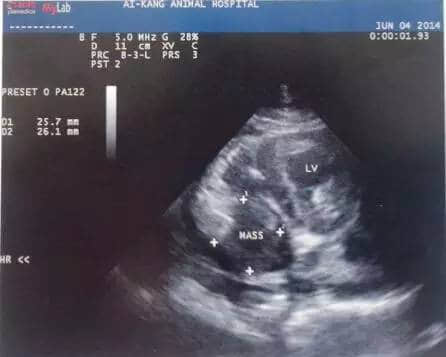

超声心动图检查是心脏肿瘤诊断最敏感的工具(图5、6),用于确定心脏肿物存在和心包积液的发生,心脏腔室的大小、形状和心室功能的继发性改变也可检查出。在二维超声心动图中,心包积液的存在有利于确认进入心包腔的心基部肿瘤,同时良好的对比度也对心腔内部的肿物有较好的显现作用。此外,多普勒超声心动图可评估相关的血流异常,确定肿物对血液回流心脏及心输出量的影响。

图5. 4岁柯基犬超声心动图,右心房内可见2.5x 65px不均质回声肿物。